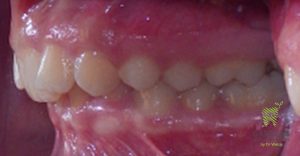

Class II malocclusion treatment correcting crowding and occlusion (bite changes)